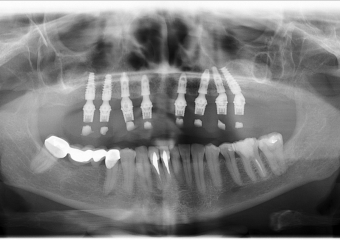

Raio - x Panorâmico Enxerto ósseo de crista iliáca

Raio - x Panorâmico Implantes